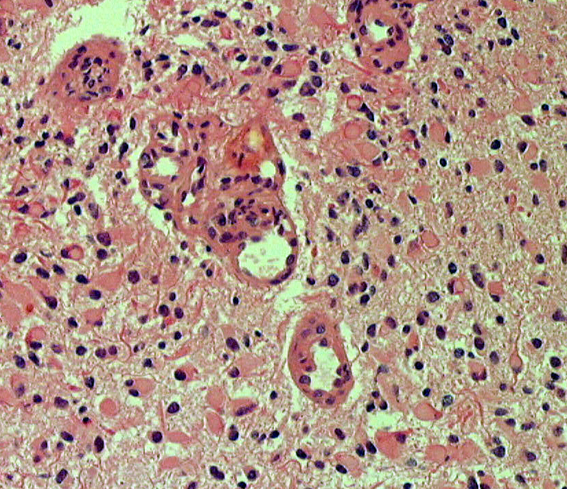

病理像です。左側の部分はperinuclear hallowが多い典型的な乏突起膠腫です。右側の部分ではびまん性星細胞腫の像ですが,その中に乏突起膠腫に特徴的なchicken wireと呼ばれる細い血管網も見られます。乏突起星細胞腫と呼ばれるのですが、腫瘍性格は乏突起膠腫と同じもので,星細胞系腫瘍には入りません。1p/19q欠失があるもののIDH変異がないのでoligoastrocytoma, NOSです。